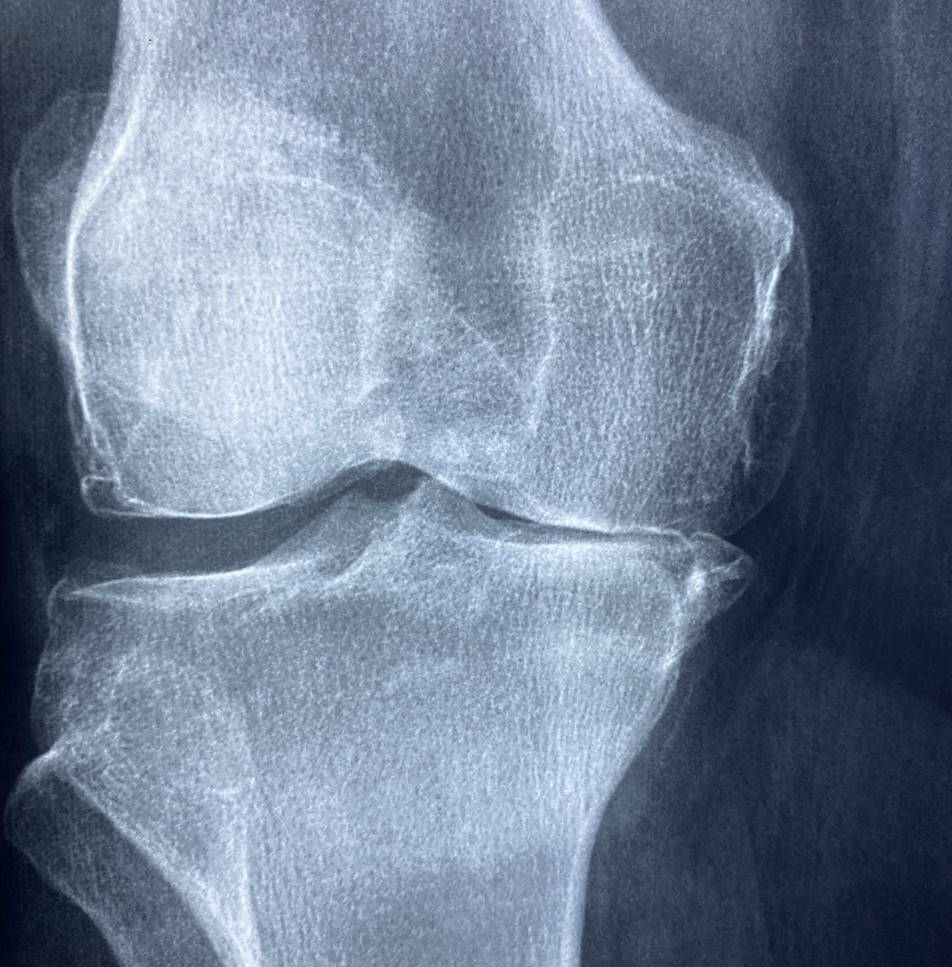

무릎 퇴행성 관절염은 관절 연골의 파괴와 관절 주변의 염증으로 인해 발생하는 만성적인 질환으로, 통증과 기능 장애를 유발할 수 있습니다. 주로 연령이 들수록 발생할 확률이 높아지며, 골관절염이라고도 불립니다. 퇴행성 관절염은 관절 부담이 큰 무릎 관절에서 특히 흔하게 발생합니다.

퇴행성 관절염은 관절 연골의 파괴로 인해 관절이 움직일 때 마찰이 발생하고, 이로 인해 통증과 염증이 발생합니다. 초기 증상으로는 관절 주변의 통증, 붓기, 관절 가동 범위의 감소 등이 나타날 수 있습니다. 진행되면서 통증이 심해지고, 관절 기능이 제한될 수 있습니다.

무릎 퇴행성 관절염은 관절 연골의 변형과 파괴로 인해 발생하는 만성적인 질환으로 아래와 같은 증상이 있을 수 있습니다.